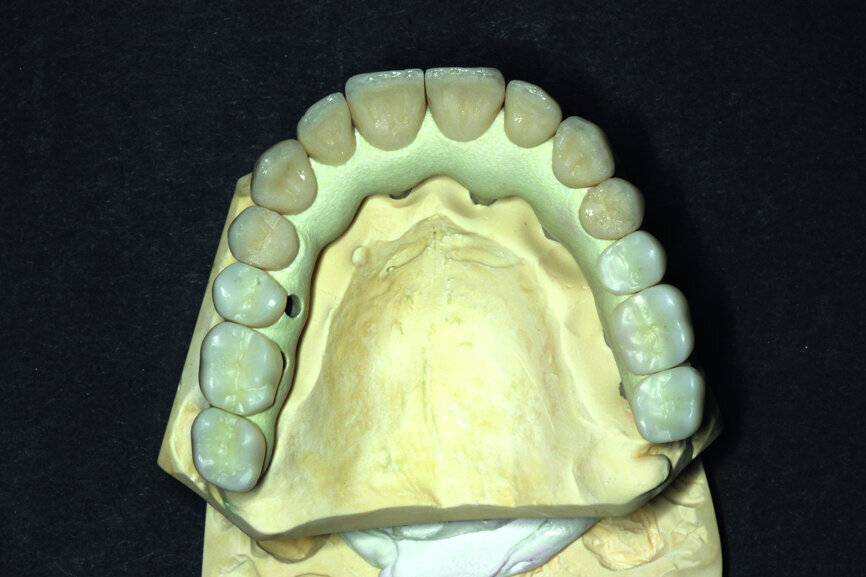

Fig. 13: Porcelain crowns prepared for testing.

Fig. 14: Porcelain crowns based on a model prior to veneering by means of a pink composite.

After this has been done, the next step consists in testing the almost ready-made crowns before the final glazing and before attaching it onto the model. As a result it is possible to make corrections, should they be necessary. Of course, one should check the proper match-up and the aesthetics on the model (Figs. 13 & 14).